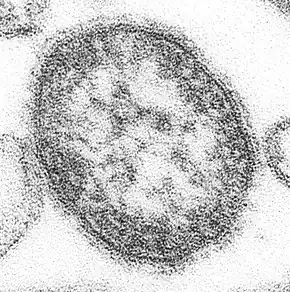

Measles is caused by the measles virus, a single-stranded, negative-sense, enveloped RNA virus of the genus Morbillivirus within the family Paramyxoviridae.[49]